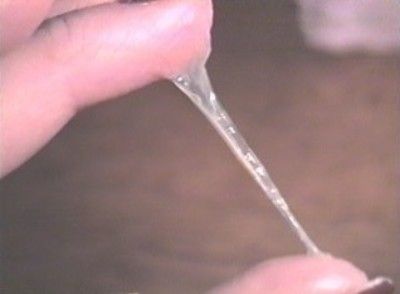

34 тижні вагітності - це початок 9 акушерського місяця. 34 тиждень вагітності: виділення в нормі повинні бути не рясними прозорими, однорідними, без запаху.

На 34 тижні вагітності виділення у вагітної жінки з піхви в нормі повинні бути не рясними, однорідними, прозорими. При виявленні будь-яких інших виділень жінка повинна проконсультуватися зі своїм лікарем.

Прозорі однорідні нерясні виділення з піхви - це норма для терміну 34 тижні вагітності. Варто починати турбуватися, якщо:

якщо лише 34 тиждень вагітності, виділення - рідина з солодкуватим запахом, то швидше за все це відійшли води. Після цього зазвичай починається родова діяльність (передчасна на 34 тижні вагітності). Навколоплідної рідини може підтікати по краплині або виливатися одномоментно. У будь-якому випадку це небезпечно для життя плода - при найменшій підозрі на відходження навколоплідних вод слід звертатися до лікаря.

Протягом цього періоду можуть виникнути слизові в'язкі виділення прозорого забарвлення. З 13 тижня вагітності жінка може помітити більш рясні виділення. Причина цього - вироблення організмом естрогену, що провокує розрідження виділень. Зараз виділення можуть стати білими, тому їх називають «белями». Основним симптомом, який говорить про безпеку виділень, є відсутність неприємного запаху, печіння і свербіння.

Ще з піхви може виділятися слиз. Це так звана слизова пробка, яка всю вагітність закриває шийку матки, а точніше її канал. Не варто плутати цю густу слиз з плодовим міхуром. Варто відзначити, що якщо така слиз з'явилася у жінки, то зовсім скоро прийде час народжувати. Боятися таких виділень не варто, тому як ніякої шкоди для малюка і майбутньої мами вони не завдають.